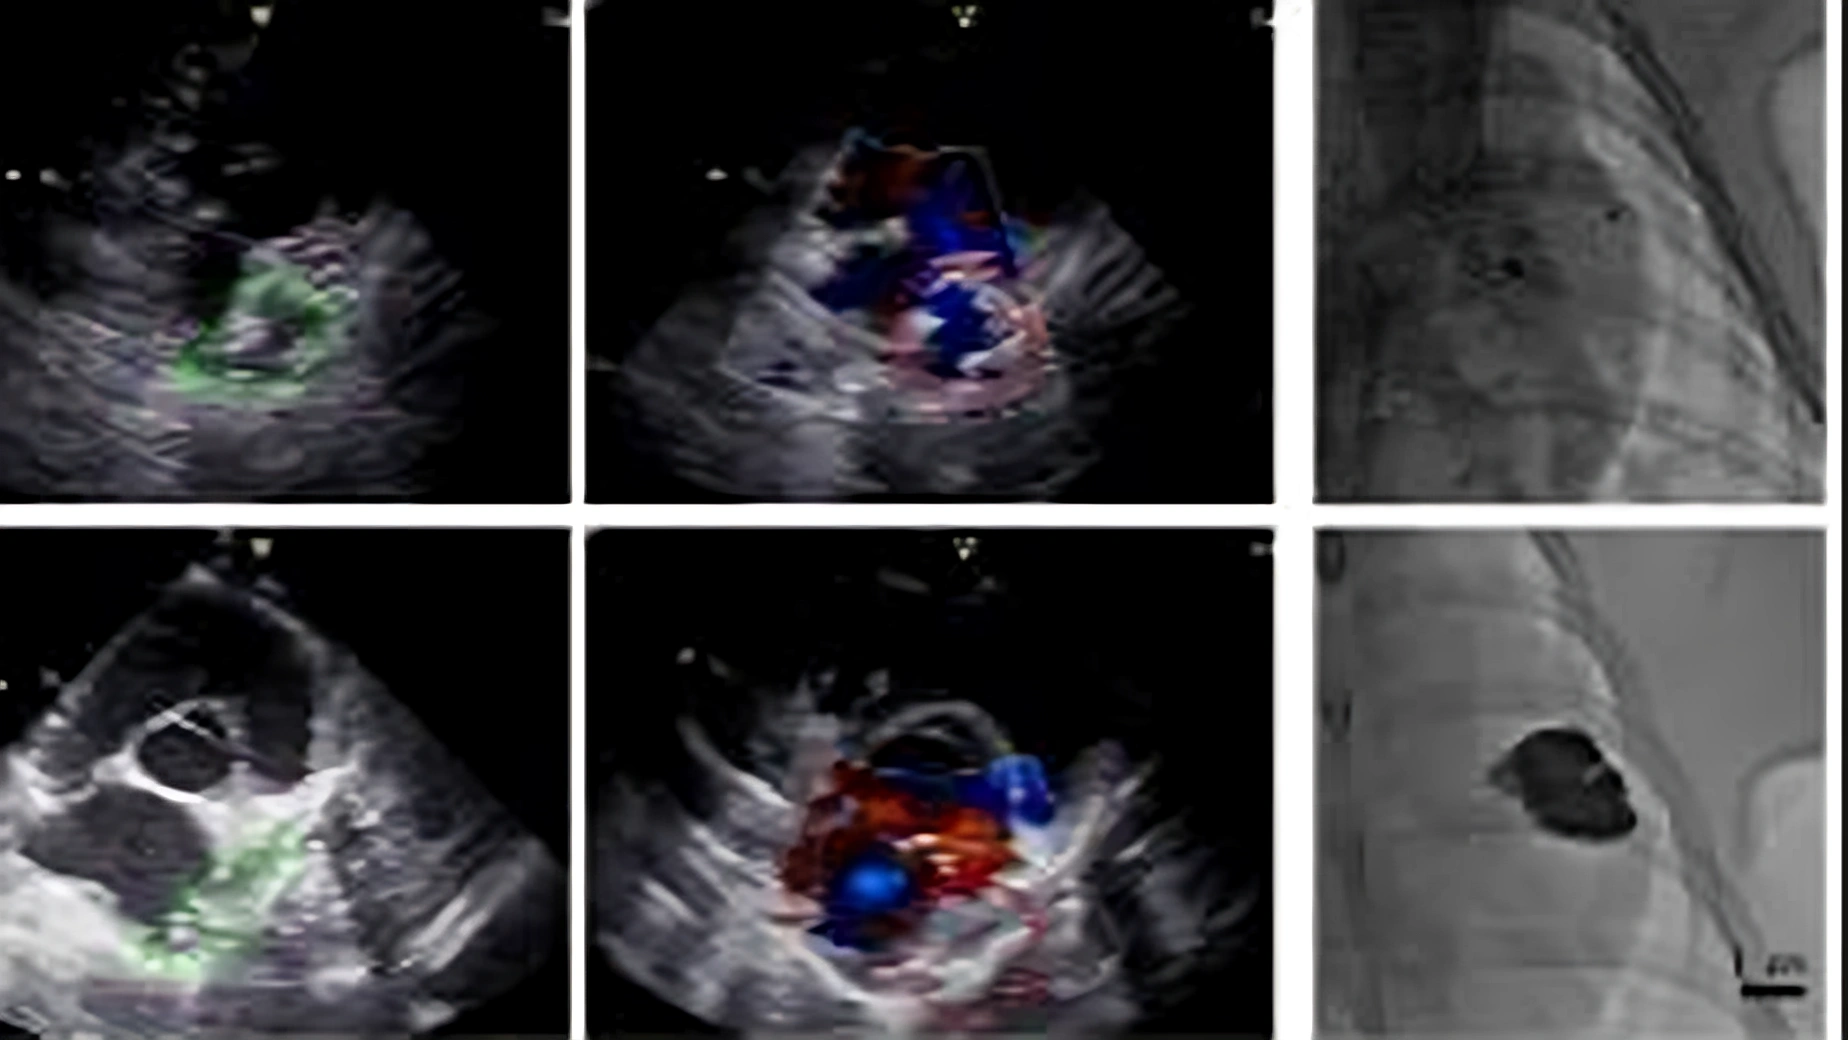

我国科研团队研发新技术开创“流体封堵”心脏介入治疗范式